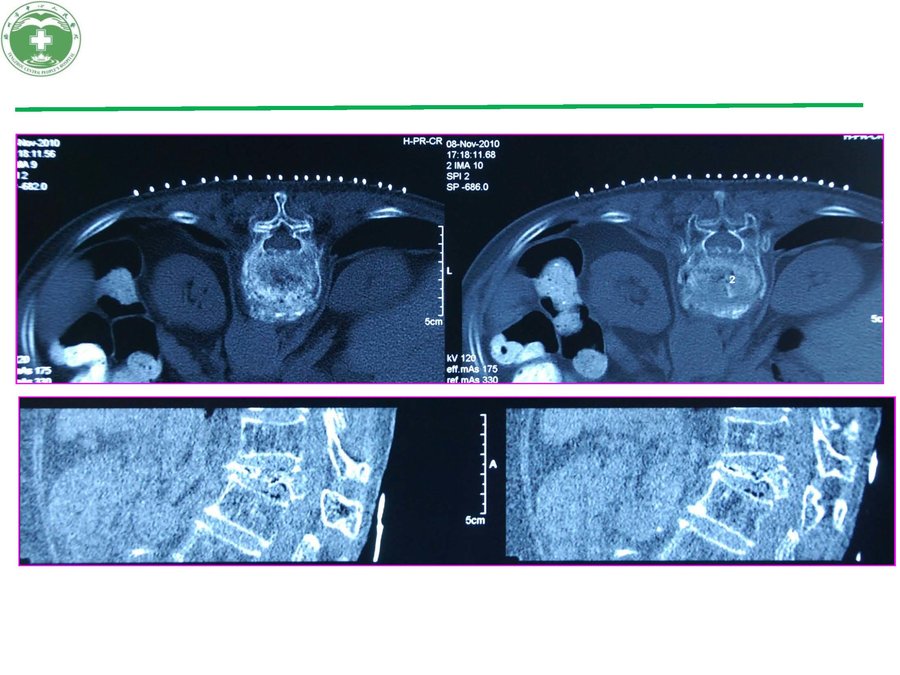

125I放射性粒子植入治疗椎体转移瘤病例报告